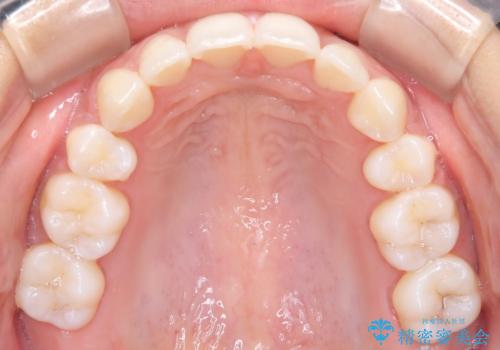

3. 【審美ワイヤー】口元を下げたいの治療後